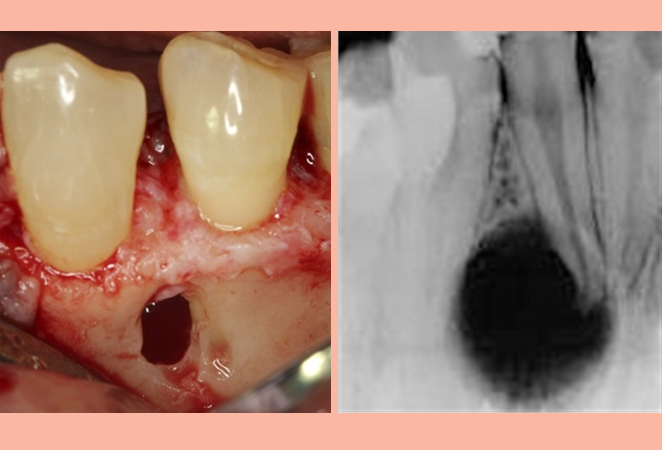

A cyst is a pathological cavity that fills with fluid or soft material and usually grows from internal pressure generated by fluid being drawn into the cavity. The mandible and maxilla, are the bones with the highest prevalence of cysts in the human body and is treated by surgery.